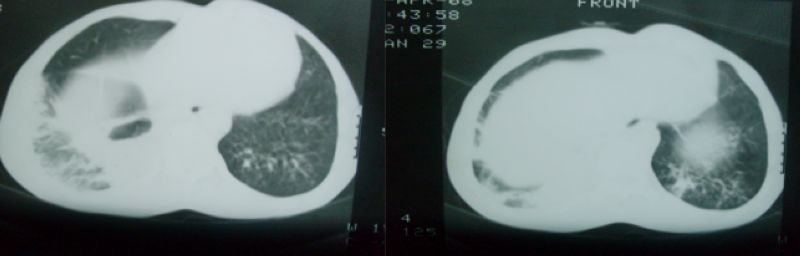

以下是引用随光逐影在2008-4-16 18:45:00的发言:[br]考虑为:肺部感染性病变;建议:抗炎治疗一周后复查。